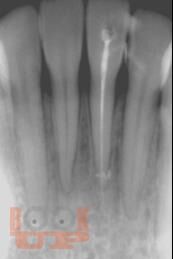

Представление материала сопровождается авторскими рисунками, фотографиями данными рентгенологических методов исследования, описанием клинических примеров.